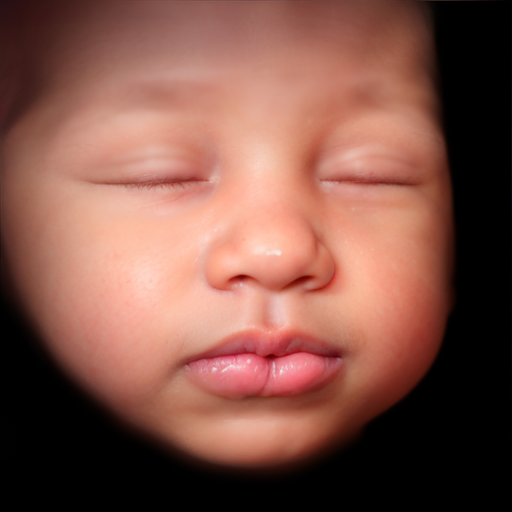

- What is an 8k Image:

Cutting Edge

Our ultrasound equipment is quality technology, bringing you crystal clear imagery to see your baby's features.